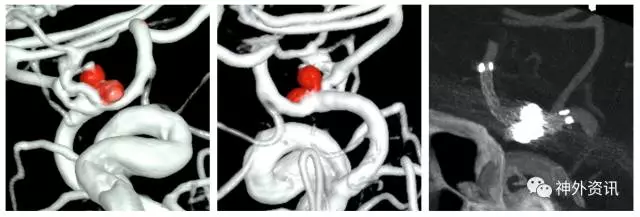

(3D血管融合:左侧额颞顶部巨大AVM,大小约10.4*6.7*5.7cm)

(治疗中,ENVOY DA导引导管置于左侧大脑前动脉A1段)

(SONIC 导管顺利超选至畸形血管巢,并且拔管顺利)

(挑战:终末血管供血,超选距离遥远,途经血管迂曲,选择使用Envoy DA)

(Envoy DA导引导管—右侧大脑前动脉A1段)

(成功超选,栓塞后拔管顺利)